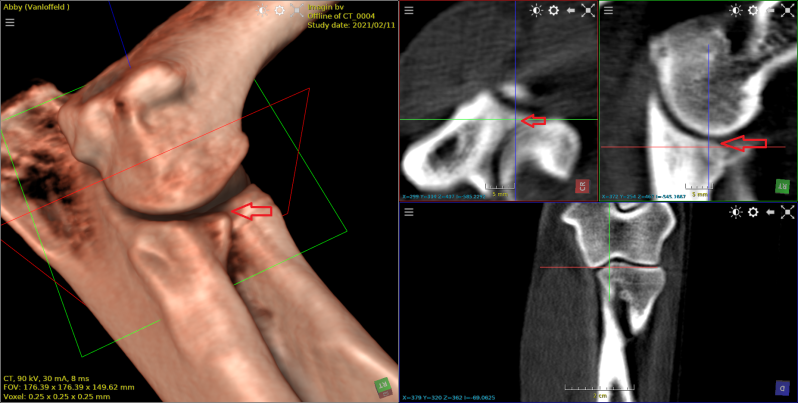

Dalmatier van 11 jaar met verlamming ten gevolge van  discus hernia op de overgang van T13  naar L1.

Eerst beelden van RX,  daarna scan beelden met en zonder contrast , vervolgens 3D beeld.